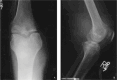

Musculoskeletal tuberculosis (TB) accounts for approximately 10% of all extrapulmonary TB cases in the United States and is the third most common site of extrapulmonary TB after pleural and lymphatic disease. Vertebral involvement (tuberculous spondylitis, or Pott's disease) is the most common type of skeletal TB, accounting for about half of all cases of musculoskeletal TB. The presentation of musculoskeletal TB may be insidious over a long period and the diagnosis may be elusive and delayed, as TB may not be the initial consideration in the differential diagnosis. Concomitant pulmonary involvement may not be present, thus confusing the diagnosis even further. Early diagnosis of bone and joint disease is important to minimize the risk of deformity and enhance outcome. The introduction of newer imaging modalities, including MRI (imaging procedure of choice) and CT, has enhanced the diagnostic evaluation of patients with musculoskeletal TB and for directed biopsies of affected areas of the musculoskeletal system. Obtaining appropriate specimens for culture and other diagnostic tests is essential to establish a definitive diagnosis and recover M. tuberculosis for susceptibility testing. A total of 6 to 9 months of a rifampin-based regimen, like treatment of pulmonary TB, is recommended for the treatment of drug susceptible musculoskeletal disease. Randomized trials of tuberculous spondylitis have demonstrated that such regimens are efficacious. These data and those from the treatment of pulmonary TB have been extrapolated to form the basis of treatment regimen recommendations for other forms of musculoskeletal TB.